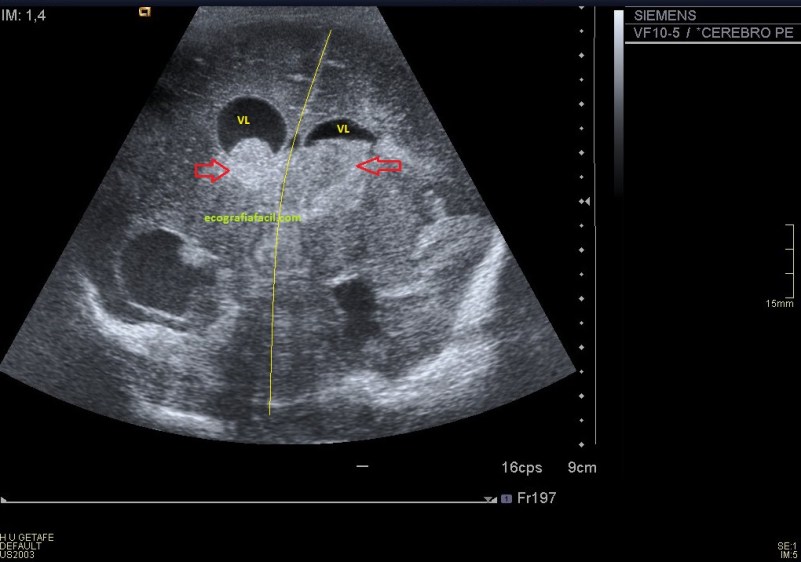

La ecografía mostró una tumoración en la región del cordón espermático derecho de unos 4cms, siendo una lesión sólida,hipoecogénica, muy bien delimitada y moderadamente vascularizada en el Doppler color.

Lo que vimos fue una masa sólida no móvil con la descripción semiológica explicada con anterioridad.

Siguiendo el protocolo habitual lo que hacemos es medir el hallazgo en los tres ejes del espacio.